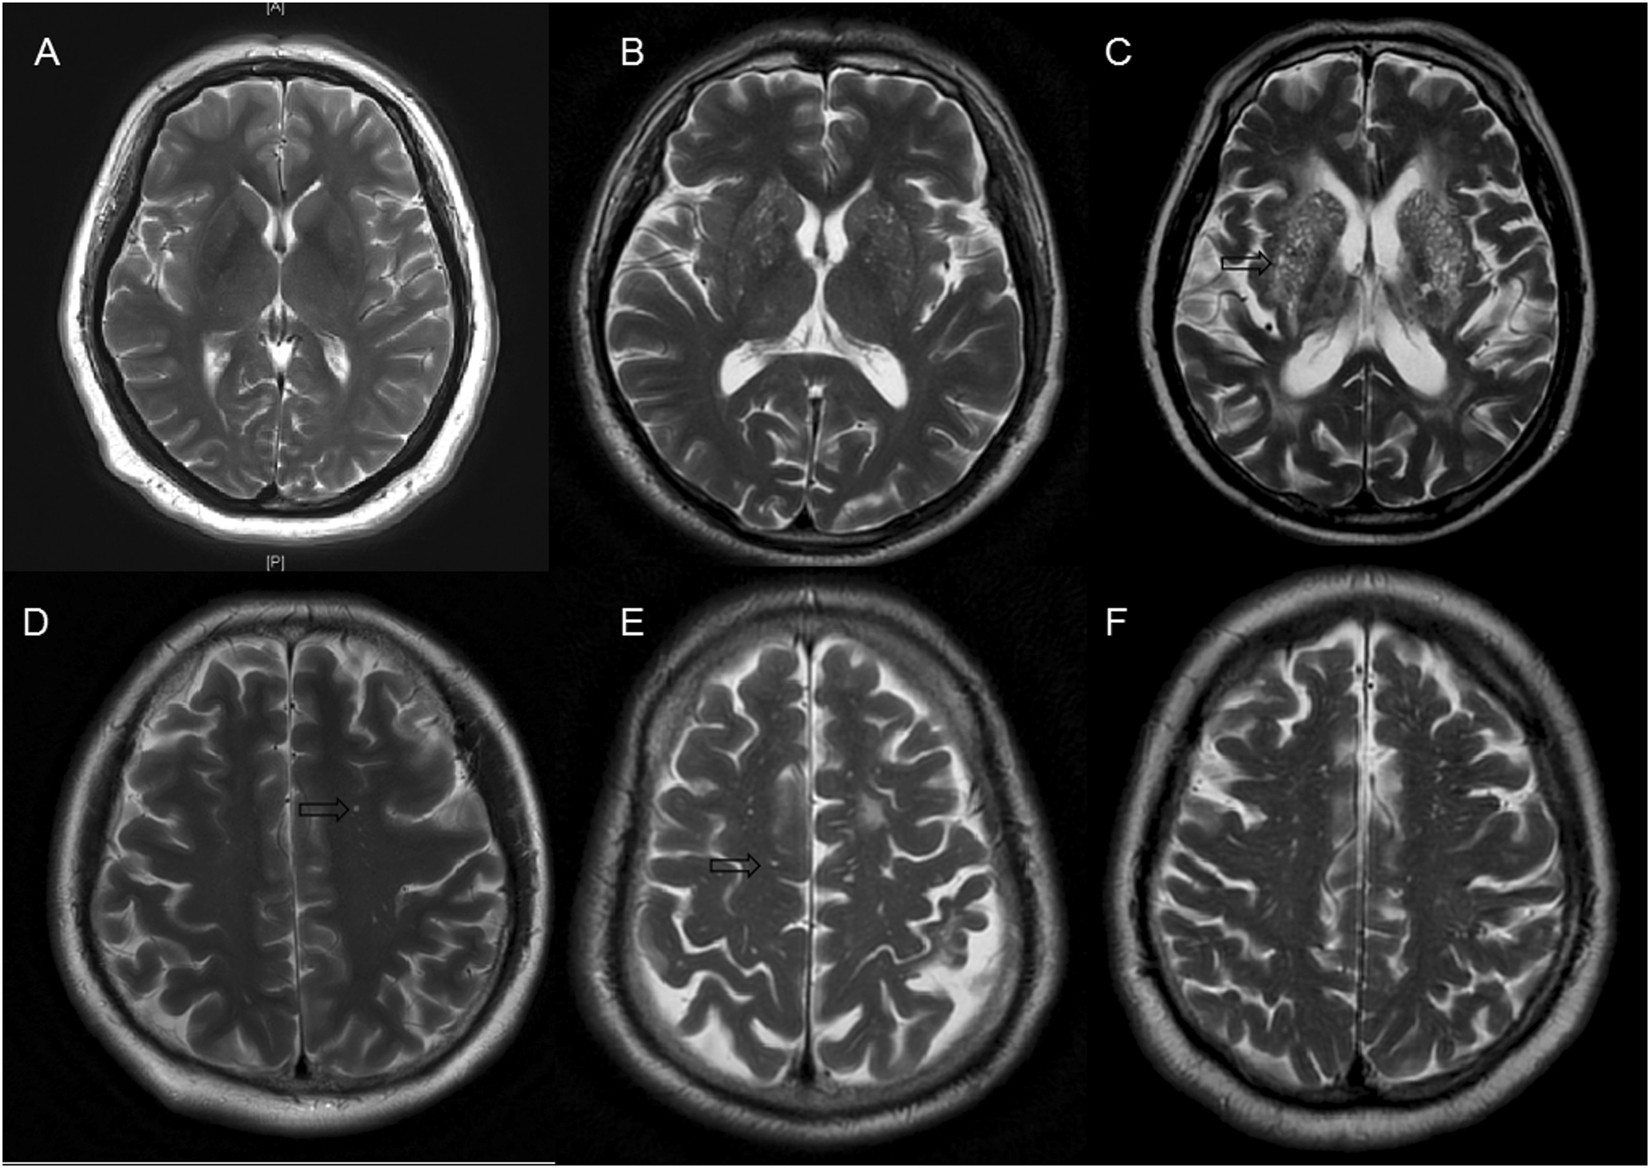

Figure 5

The severity of enlarged perivascular spaces in basal ganglia and white matter. (A) Mild in basal ganglia; (B) moderate in basal ganglia; (C), severe in basal ganglia; (D), mild in white matter; (E), moderate in white matter; (F), severe in white matter. The arrows were pointing to enlarged perivascular spaces, which appear as punctate or linear identical signal intensities that are similar to cerebrospinal fluid on MRI sequences.